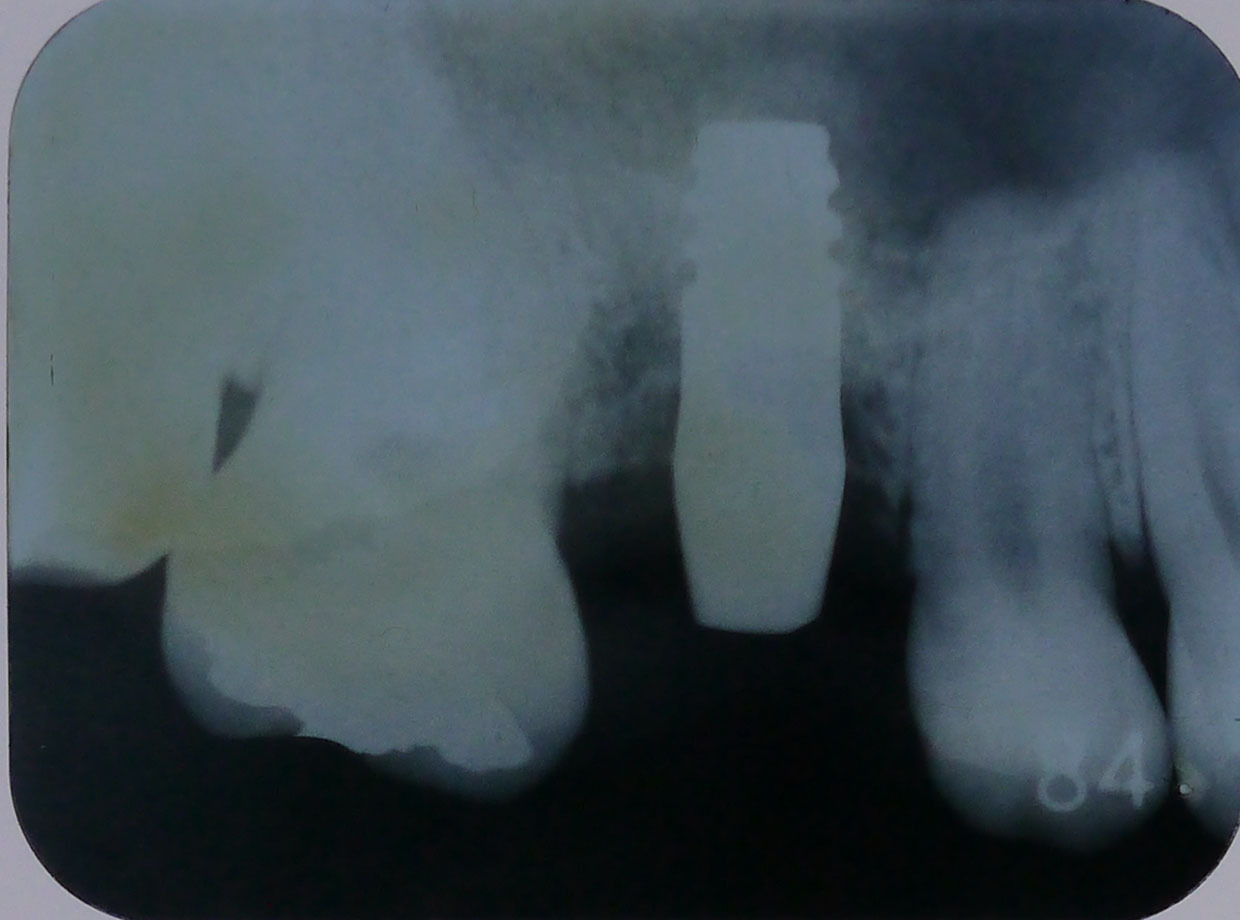

レントゲン画像3

平成29年12月6日、5年経過後の定期検診時のレントゲン画像

右上6番、インプラントの先端近くまで骨があり、十分機能している